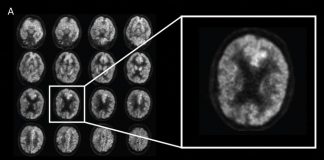

알츠하이머 치매, AI로 조기 진단 성공

전 세계에서 수천만 명이 앓고 있지만 조기 진단이 어려운 알츠하이머병을..